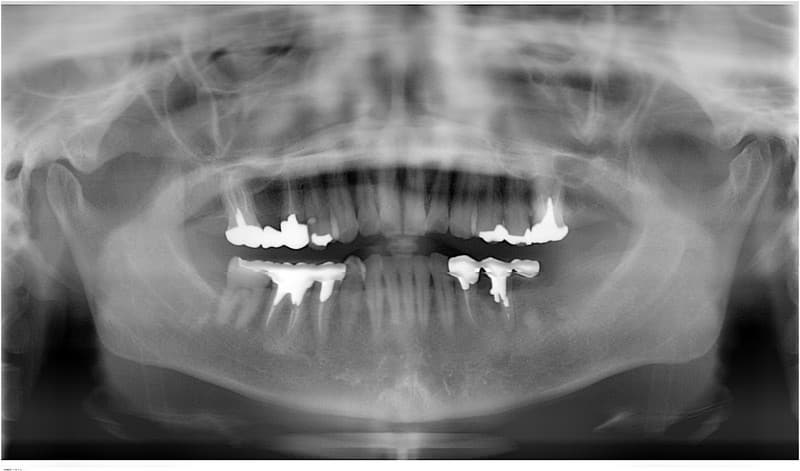

完全に歯がない場合

従来の治療

土台になる歯がないため総入れ歯となります。

うまく合わない場合は、食事がおいしくない、うまく話せない、外れやすいなどの問題が生じることがあります。

インプラント治療

インプラントを土台にして入れ歯を安定させ、動かず、しっかりした義歯にすることが出来ます。

また、あごの状態によってはインプラントによって一本ずつの歯を自然な状態で再建することも可能です。